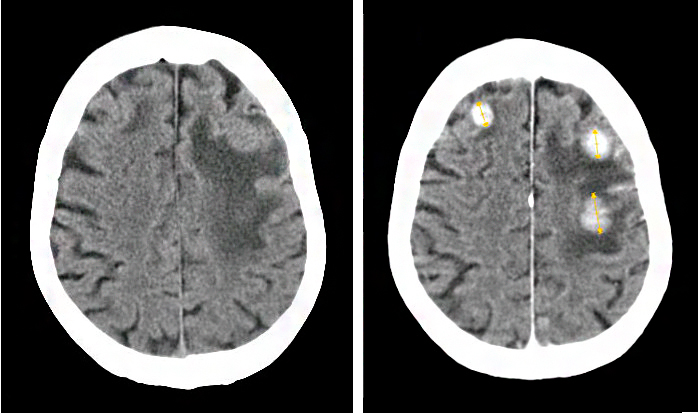

- Компьютерная томография может визуализировать даже бессимптомные поражения у больных с экстракраниальными повреждениями (которые находятся на поверхности органа).

«Золотой стандарт» в диагностике метастатического рака головного мозга — магнитно-резонансная томография (МРТ). Во время этого исследования получают изображения внутренних структур тела, используя сильное магнитное поле. По снимкам врач может судить о количестве, размерах, расположении метастатических очагов.

- КТ. Этот метод помогает визуализировать даже бессимптомнее поражения у пациентов с экстракраниальными повреждениями (находящимися на поверхности органа);